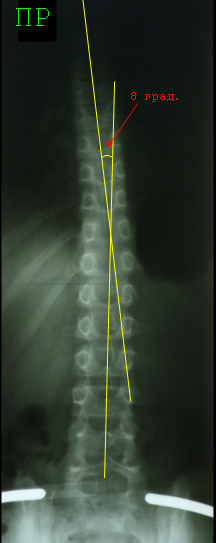

Прямая

рентгенограмма позвоночника ребенка 8 лет, сколиотическая деформация в нижней

части грудного отдела, некомпенсированная, С – образная, ротация позвонков отсутствует. Выполнение расчерчивание по Фергюсону –

просто, изящно и красиво. Угол дуги составил 8° - в

границах первой степени. Метод Фергюсона

является основным в работе с детьми до 10 лет.